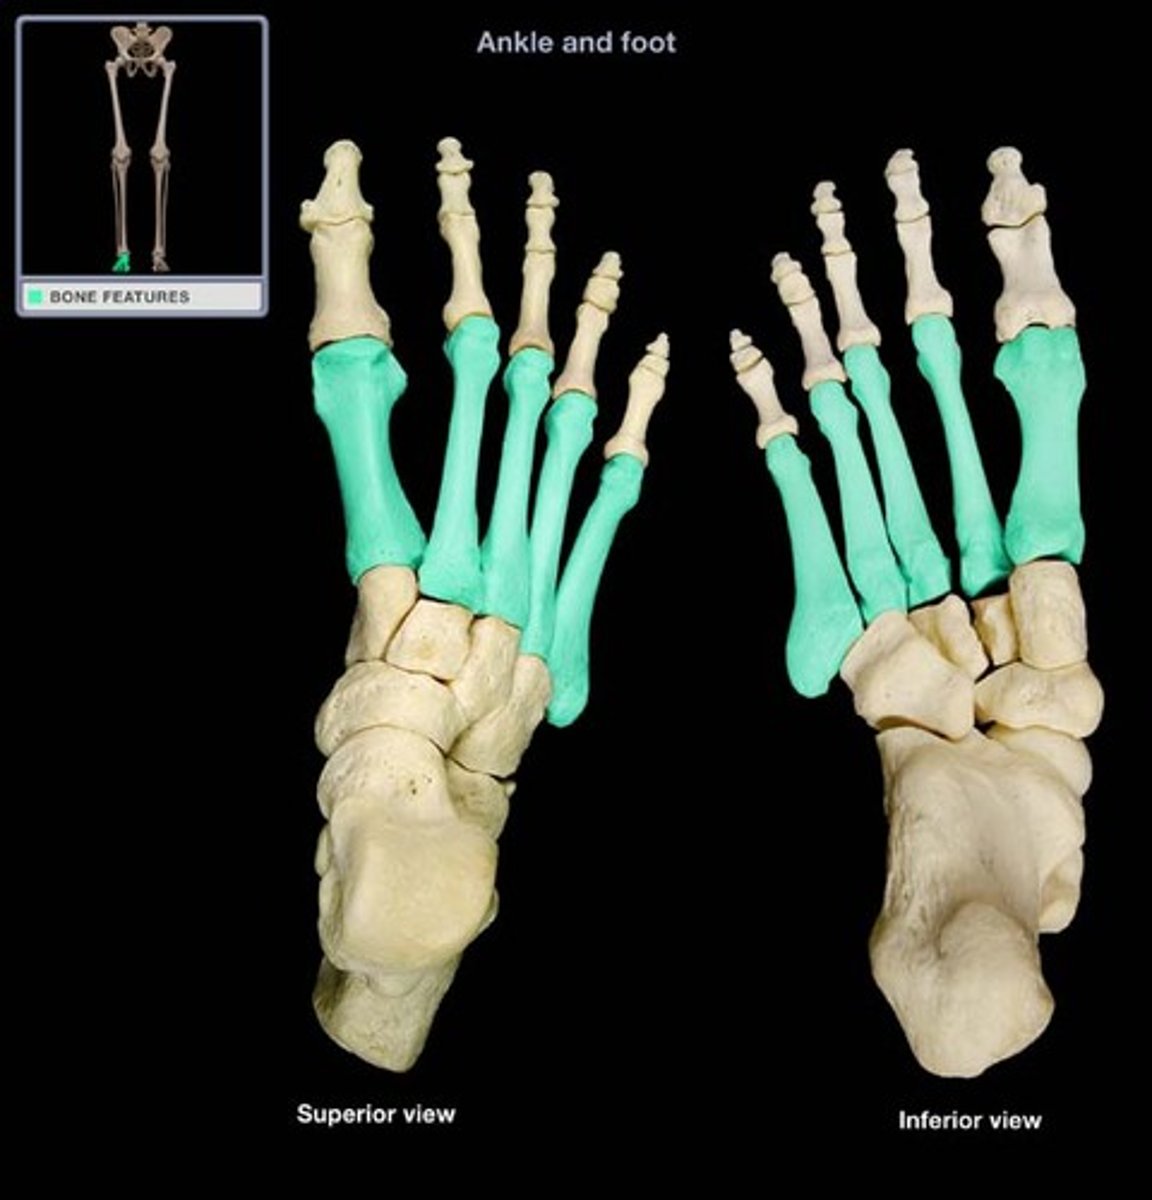

metatarsals